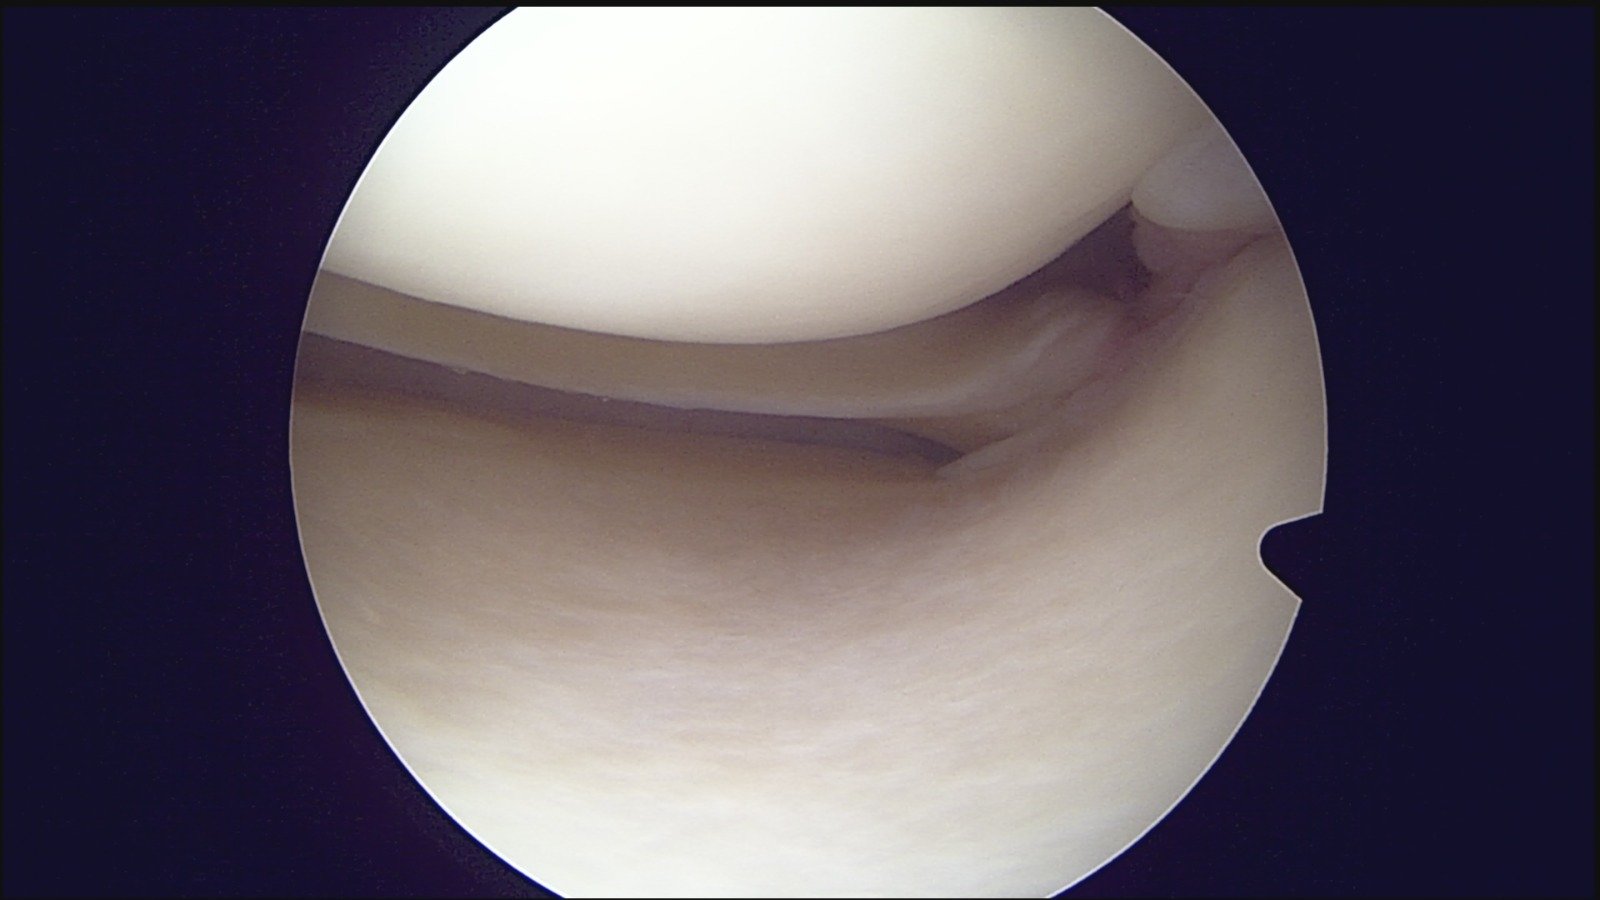

GalleryShoulder rotator cuff repair Meniscus root repair Meniscus repair Bankart repair for recurrent shoulder dislocation ACL reconstruction Machines Instruments